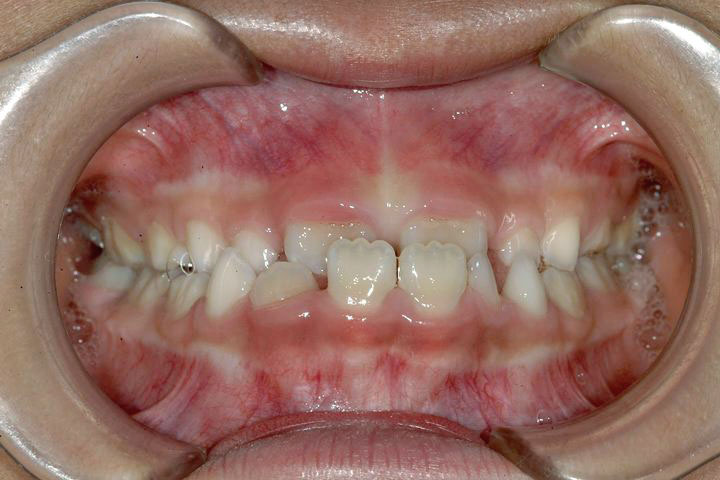

受け口を主訴に来院された幼稚園年長の女の子です。上顎前歯が未萌出であったため、その萌出を待って小学校2年生の時に矯正治療を開始いたしました。前歯部被蓋改善をリンガルアーチとチンキャップで行った後、定期観察を経てデーモンシステムで最終的に配列を行いました。下顎前歯が3本しかなく、一本の先欠(先天性欠損)を認めましたが、その空隙も閉鎖することができました。前歯被蓋の安定までに2年、その後中学1年生までの定期観察を経て、エッジワイズ治療期間で2年を要しました。